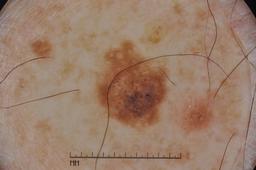

Evaluation set from the ML challenge: SIIM-ISIC Melanoma Classification.